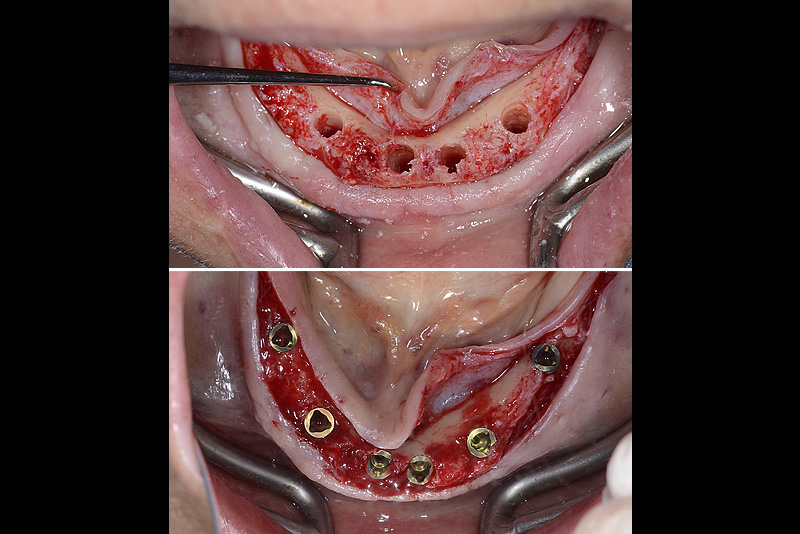

PREMESSA: in seguito all’estrazione dell’incisivo laterale superiore di destra, resasi necessaria per cause batteriche, si decide di affrontare il caso con il posizionamento di un impianto in sostituzione dell’elemento mancante dopo guarigione del sito infetto. Con tecniche rigenerative sia dei tessuti ossei mancanti a causa dell’infezione pregressa, sia dei tessuti gengivali che appaiono inizialmente troppo spostati in alto, si ripristina una corretta morfologia delle parabole (contorni) gengivali e delle papille interdentali (triangoli di gengiva tra due denti vicini).

Vengono utilizzati 2 tipi di provvisori: il primo, cementato ai denti vicini, viene utilizzato dal momento dell’estrazione del dente fino ad impianto osteointegrato (circa 6 mesi); il secondo, avvitato direttamente all’impianto, ha una funzione di prova estetica ma soprattutto di guida per la maturazione dei tessuti gengivali peri-implantari portandoli verso la maturazione completa prima di posizionare la corona finale in disilicato di litio.